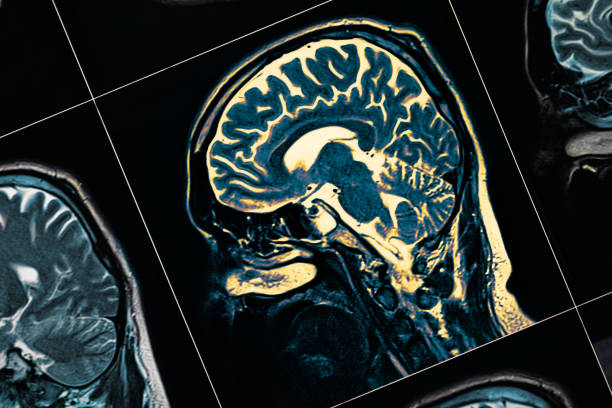

其他專家將參與為您的孩子進行全面的體檢、 血液檢查、心理健康測試、大腦成像測試和其他檢查。它們都是找到正確診斷并制定治療計劃以幫助您的孩子控制疾病的關鍵。